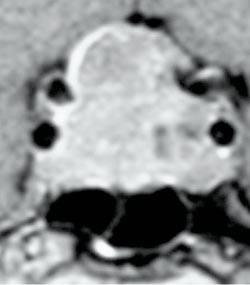

Ved mistanke om svulst i hypofysegropen utføres MR. De fleste adenomer er også synlige på CT, som brukes ved kontraindikasjoner mot MR (pacemaker, magnetiske klips osv.). MR gjøres med 3 mm snittykkelse i sagittal- og koronalplanet før og etter injeksjon av gadoliniumkontrast, ev. supplert med aksiale T1- og T2-vektede bilder (fig 1 – 3). Ved synsaffeksjon skjer utredningen av svulsten i samarbeid mellom endokrinolog (koordinator), nevrokirurg, nevroradiolog, og øyelege. Pasientene drøftes på samarbeidsmøter, såkalte hypofysemøter (fig 4).

Operasjon

I over 90 % av tilfellene foretas en transsfenoidal tilgang som innebærer at det føres selvholdende spekel inn i nesen, enten via et nesebor eller via en incisjon sublabialt, til sinus sphenoidale (35). Operasjonen foregår i narkose ved hjelp av operasjonsmikroskop, og gjennomlysning blir brukt for å sikre korrekt retning av instrumentene i sagittalplanet. Når hypofysegropen åpnes må kirurgen være omhyggelig med å holde seg i midtlinjen, for å hindre skade på a. carotis interna.